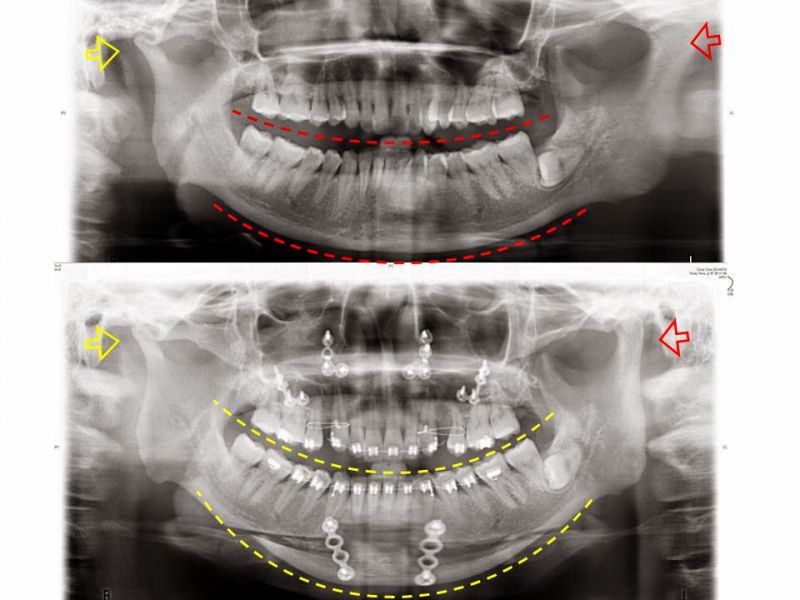

下图影像可以看到两侧的颞颚关节有明显不同(黄色箭头较小为异常侧,红色箭头较大为正常侧。上图红色箭头所指处是因对焦模糊所以形状改变) 手术本身并没有造成关节附近的骨骼、肌肉改变,但是对牙齿的排列弧度以及脸部轮廓的影响可以由上下图中的弧线比较得知,微笑曲线也同时改善。